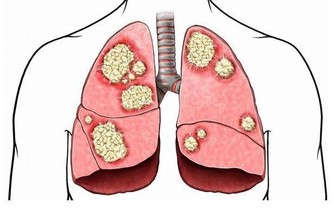

①心臟冠狀動脈堵塞,人體容易出現心肌梗死、心律失常、猝死等現象。

②腦動脈血管堵塞,或發生動脈硬化,可能出現腦血栓、腦梗死等現象,患者會癱瘓、昏迷、死亡等。

③腎動脈血管堵塞,或發生動脈硬化,可能導致腎功能衰竭、尿毒症等現象,患者往往需要進行洗腎、透析等,嚴重時還可能要換腎。